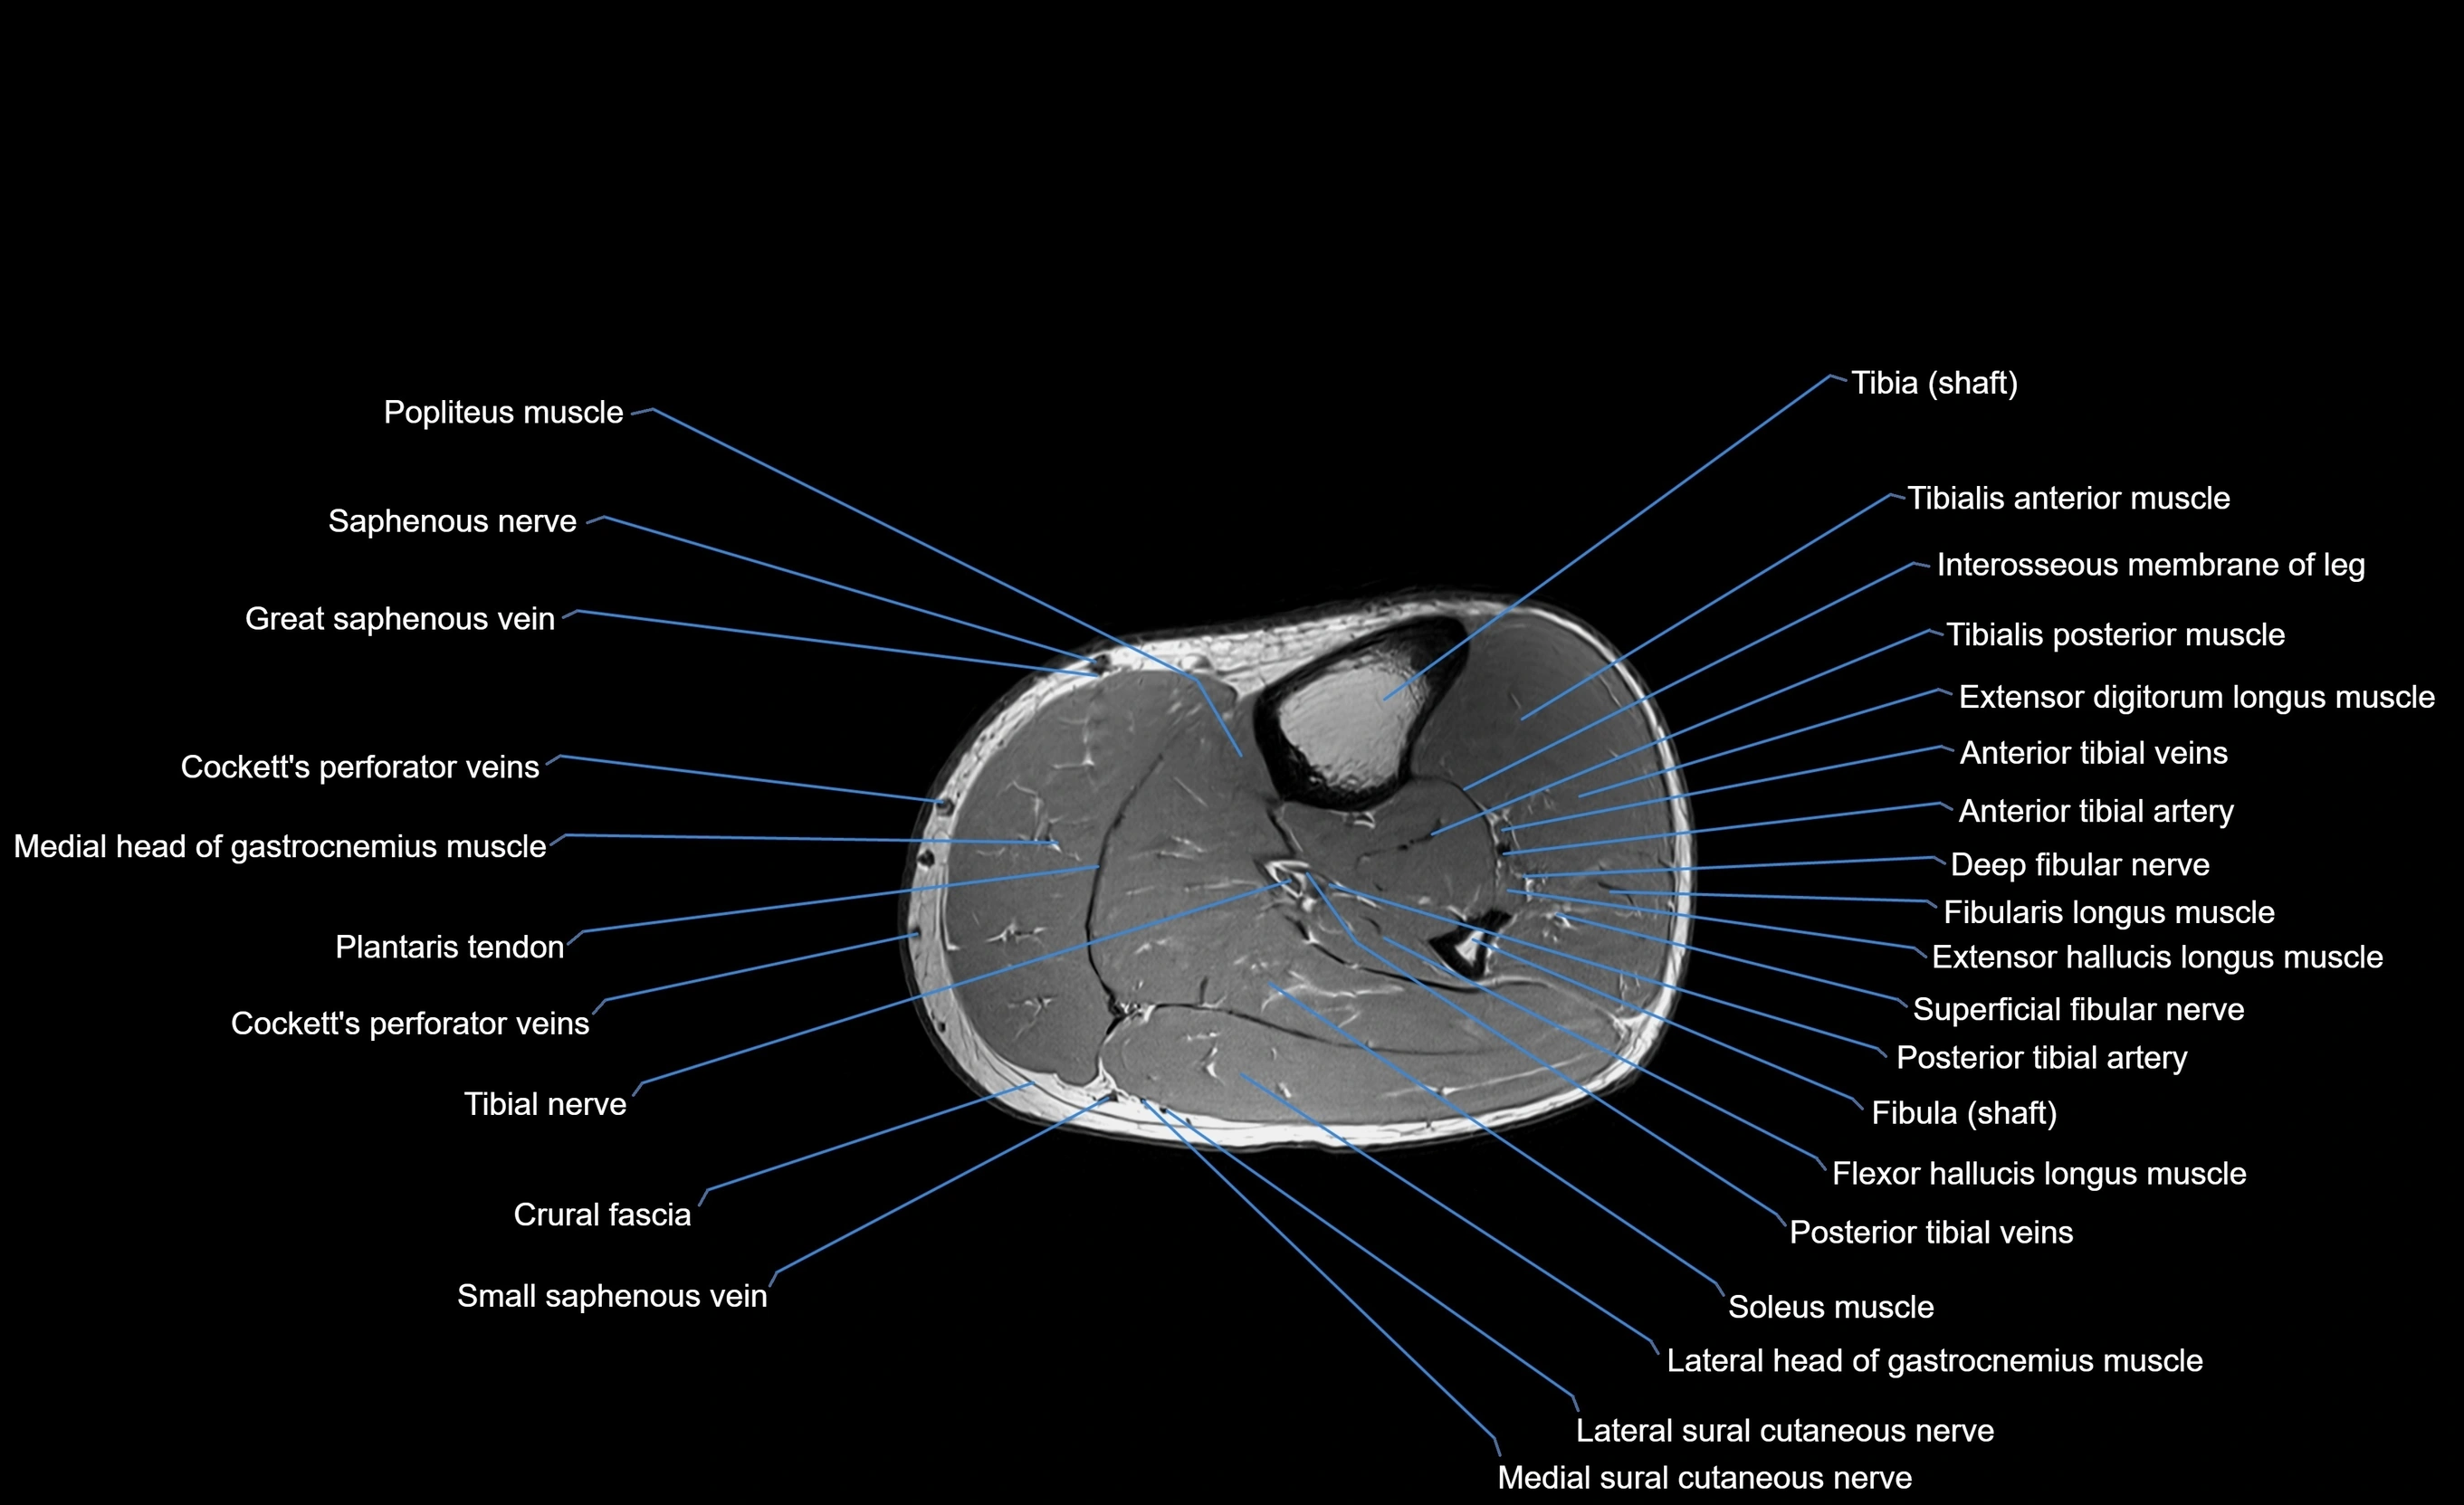

MRI image